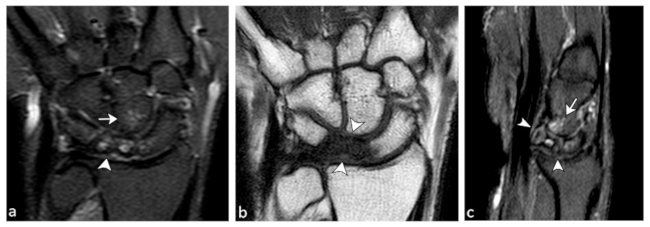

La enfermedad de Kienböck es una afección caracterizada por necrosis avascular del hueso semilunar. Presenta un mecanismo patofisiológico multifactorial, con factores anatómicos que predisponen al desarrollo de la enfermedad, como la varianza cubital negativa y la morfología rectangular o cuboidea del semilunar.21,22

Entre los mecanismos para el desarrollo de la ON del semilunar se encuentra la lesión de las arterias dorsales y volares, ya sea por afectación de las estructuras capsulo-ligamentarias o por fracturas/luxaciones del hueso semilunar. También se puede presentar por lesión neurovascular de las terminales nerviosas carpianas, provocando una reacción vasomotora con una vasodilatación (estasis vascular/descalcificación ósea) - vasoconstricción (desencadena un infarto óseo).22

Las fracturas del semilunar por compresión secundarias a micro-traumatismos repetidos, que comprometen las entradas vasculares, o secundarias a una varianza cubital negativa, provocan una alteración en el reparto de las presiones en la articulación radio-carpiana, sometiendo a una mayor presión de la mitad cubital de la carilla articular radiosemilunar.22

La enfermedad de Kienböck se puede evaluar morfológica y funcionalmente, siendo importante para estimar la progresión de la enfermedad y elegir el tratamiento más adecuado. La evaluación morfológica se realiza con la clasificación de Lichtman (►Tabla 5), de acuerdo a los hallazgos por RX, TC y RM (►Figs. 11 y 12).22,23 Es altamente confiable y reproducible y tiene mayor relevancia clínica porque ayuda a determinar el tratamiento más adecuado.